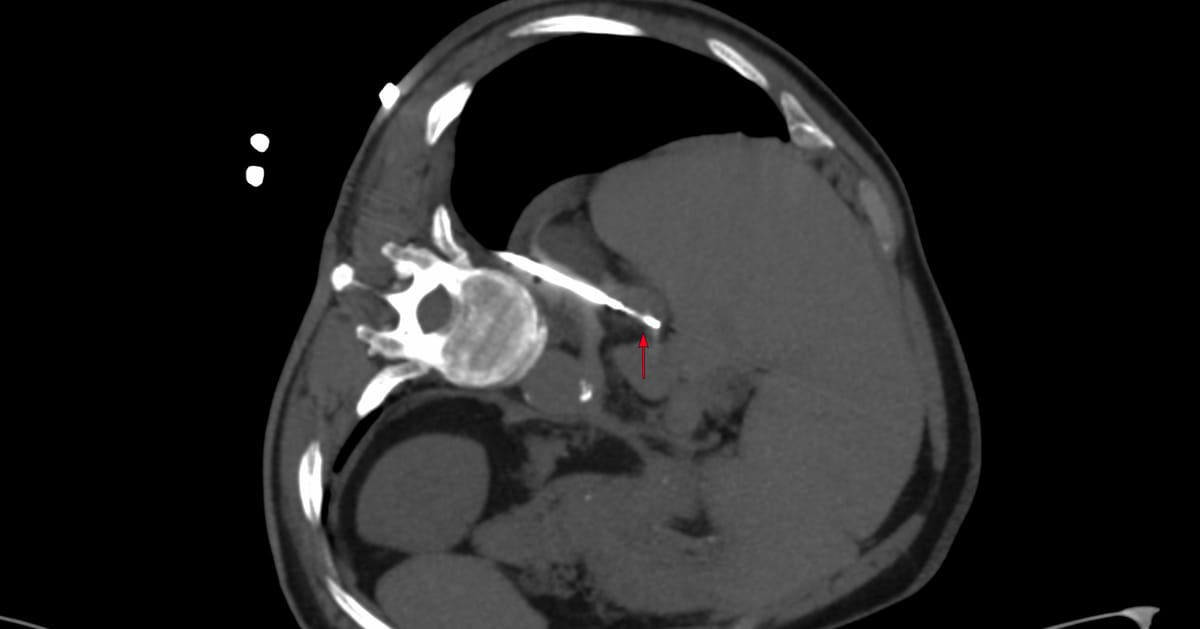

Current Case:

61-years old treated for Ca stomach with a Whipple’s had a new active node on a FAPI PET/CT.

What would be your approach, given the overlying leash of bowel loops and overlying vessels?

The video below describes the case. The biopsy was performed using multiple techniques, including the blunt-tip, the fixed-point methods and intra-procedural intravenous contrast.